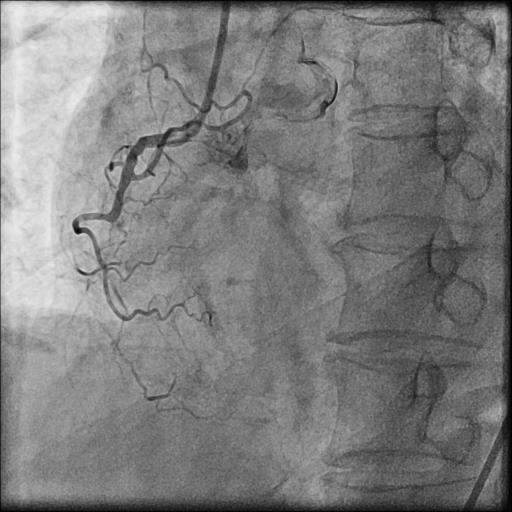

Coronary Angiogram done elsewhere via right femoral artery with JR and AL 1.0LMCA NormalLAD Type III Vessel. Normal. LCx: Non dominant, NormalRCA: Chronic Total Occlusion from midpart. Distal filling by retrograde from Left system.J-CTO score 3

LMCA was engaged with JL 4.0 7 Fr. catheter. First septal collateral was used to reach the distal cap of the lesion using Sion black, Runthrough extrafloppy and Fielder XT-R wire with microcatheter but could not penetrate the distal cap. The lesion could not be crossed with Gaia second and Gladius¢ç Mongo¢ç wire. Antegrade approach was decided to a cross the lesion with Gaia second wire. Antegrade approach caused a dissection resulting in a sub intimal hematoma which extended into the Posterolateral branch. This dissection and the hematoma straightened the vessel near the distal cap. Now this straightening allowed the ASAHI Gladius¢ç Mongo¢ç wire to cross the distal cap retrogradely. The Gladius¢ç Mongo¢ç wire could not be positioned into the true lumen. Now to avoid further dissection proximally the Mongo wire was exchanged with Pilot 150 wire. This wire could cross the proximal cap and finally into the guide catheter. Pilot 150 wire was exchanged with Choice Floppy LS 300 cm which was externalized. A finecross microcatheter was advanced over this wire antegradely. Retrograde microcatheter removed and rest of the case was completed via antegrade approach over Runthrough NS Floppy wire. Lesion was predilated with 2.5x12 mm NC balloon @ 12 atm. Promus Elite 2.75x38 mm DES deployed in mid to distal RCA @ 12 atm. An overlapping stent Xience Xpedition 3.0x28 mm DES deployed from ostium to mid RCA @ 11 atm. Post dilatation with 3.25x10 mm NC balloon @ 11 atm. Distal TIMI III flow achieved.